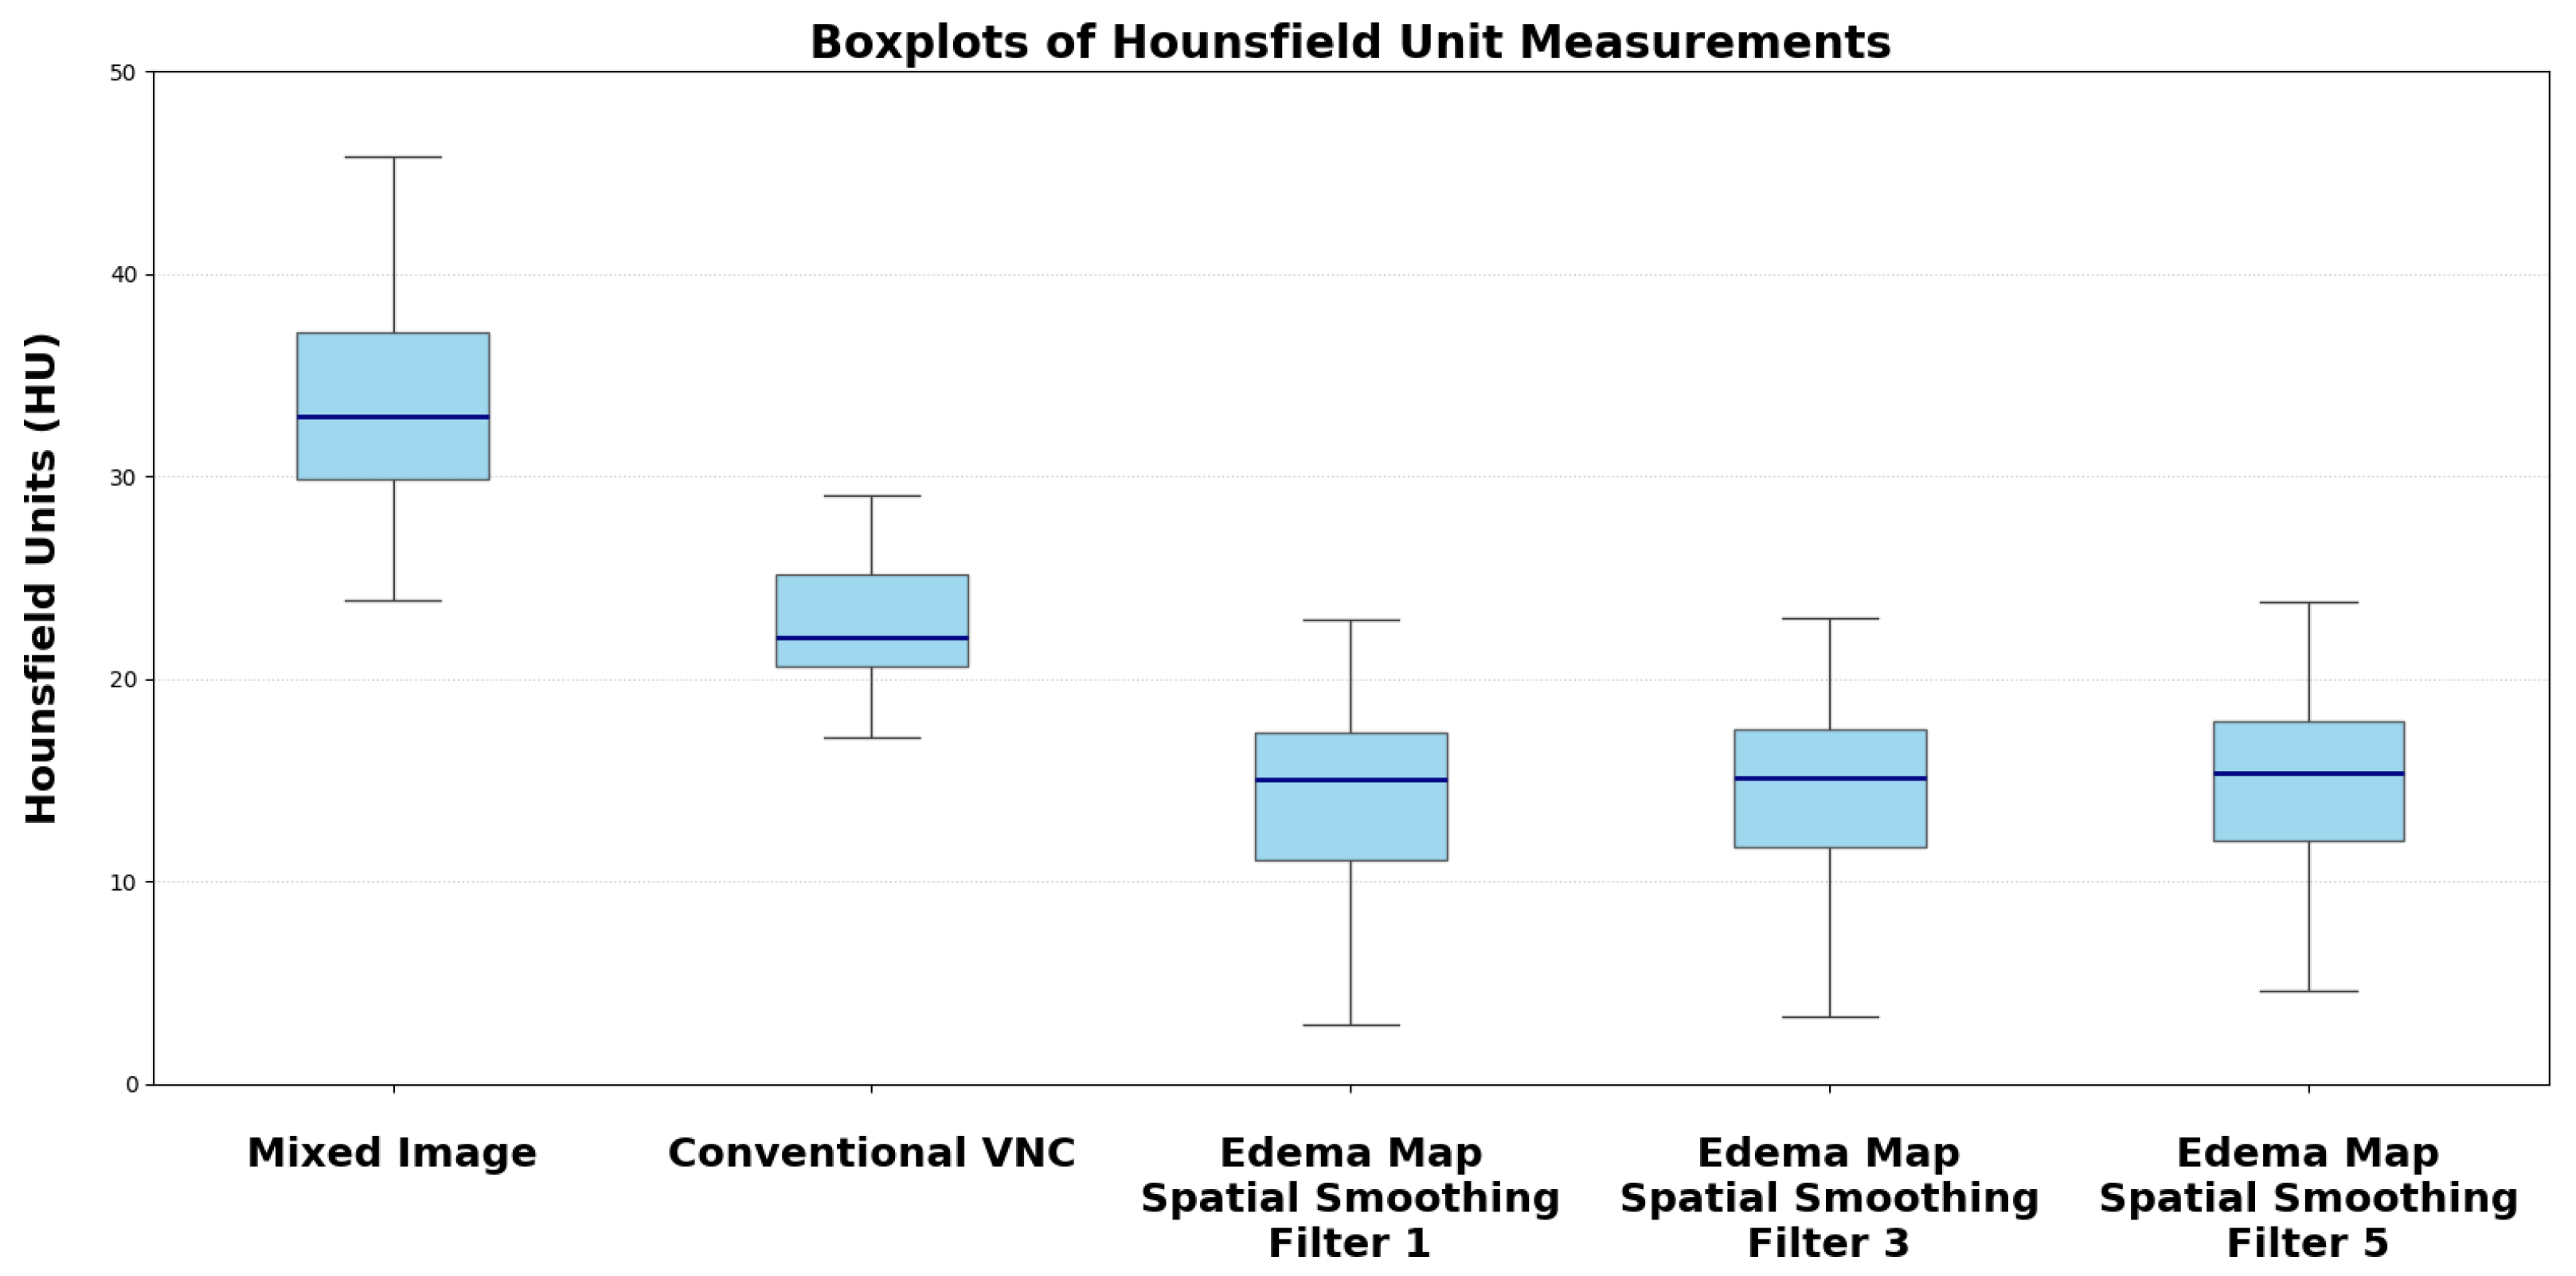

| Reconstruction | Median HU (SD) | p-Value vs. Mixed Image/VNC |

|---|---|---|

| Conventional Mixed Image | 33.73 (4.58) | |

| Default VNC | 22.96 (3.85) | |

| Edema Map Resolution 1 | 14.39 (4.98) | |

| Edema Map Resolution 3 | 14.50 (3.75) | |

| Edema Map Resolution 5 | 15.05 (2.65) |